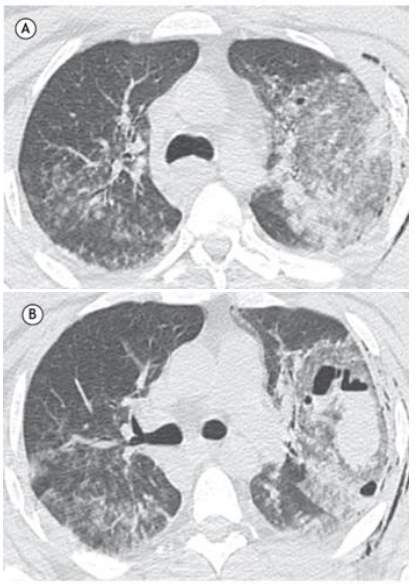

Homem de 38 anos, sem comorbidades, deu entrada no pronto-socorro após acidente de moto, queixando-se de dor torácica, tosse e hemoptise.

O paciente realizou tomografia computadorizada como parte da rotina diagnóstica.

O resultado foi: